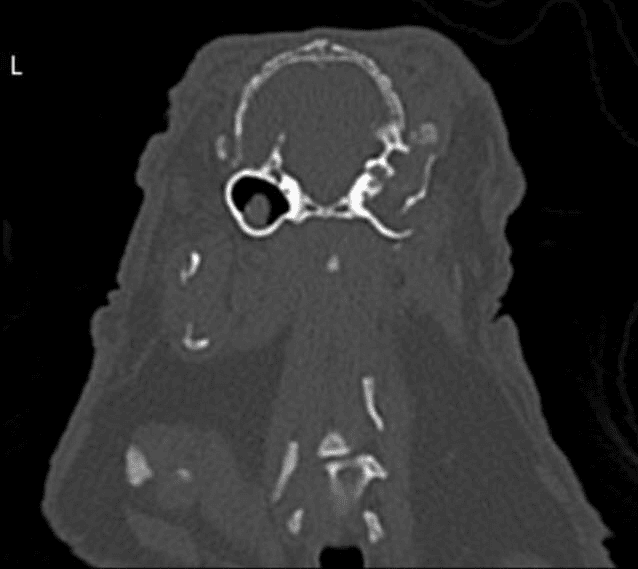

Dwarf lop rabbit after dental surgery – such suffering is avoidable through responsible breeding!

Ear infections

Inflammation occurs in up to 80% of lop-eared rabbits. Due to their altered ear anatomy, the drooping ears cause a kink in the ear canal. This prevents normal drainage of secretions, leading to chronic infections in the lower part of the canal, often hidden behind the characteristic fold.

These infections can spread through the eardrum and lead to inflammation of the middle ear and even the inner ear.

Findings from recent studies:

- More than 16% of all lop-eared rabbits have abscesses at the base of the ear (while not a single upright-eared rabbit does).

- In 87% of lop-eared rabbits, pus was macroscopically detectable in the ear canal, whereas none was found in rabbits of other breeds.

- In nearly 8 out of 10 lop-eared rabbits that were not presented for ear infections, the ear canal was still filled—compared to only 0.3 out of 10 upright-eared rabbits.

- More than 80% of lop-eared rabbits have a severely narrowed ear canal. In almost none of them was the eardrum visible in the study (compared to 35% in upright-eared rabbits).

- Bacteria were detected in 88% of lop-eared rabbit ears (in all cases cocci, sometimes also rods).

- Neutrophils were found in 58% of lop-eared rabbit ears (compared to only 3% in upright-eared rabbits). Lymphocytes were present in 33% of ears (0% in upright-eared rabbits). Additionally, 5% of lop-eared rabbits had erythrocytes in the ear (0% in other breeds).

- However, only 7% of lop-eared rabbits showed a pain response when their ears were palpated.